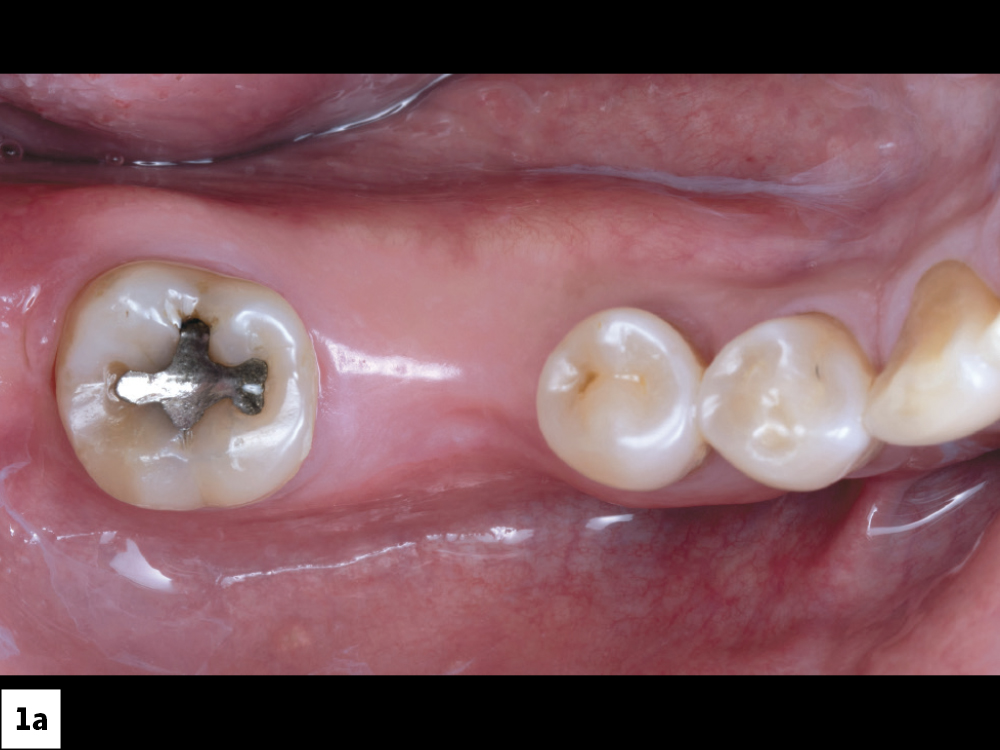

Ted Vo, a dental technician in the Glidewell implant department, came to our clinic because he had been missing tooth #30 for several years. He reported difficulty eating and was self-conscious about the edentulous space that sometimes showed when talking and laughing. Except for an occlusal amalgam restoration on #31, the adjacent teeth were healthy. My treatment plan called for an implant and a BruxZir® Esthetic Zirconia screw-retained crown, which the patient accepted.

Figures 1a, 1b: Upon clinical examination, the ridge appeared to have adequate width, though there was some narrowing near tooth #29. A CBCT scan and intraoral measurements allowed me to accurately determine ridge dimensions and evaluate whether there was adequate bone volume for implant placement.